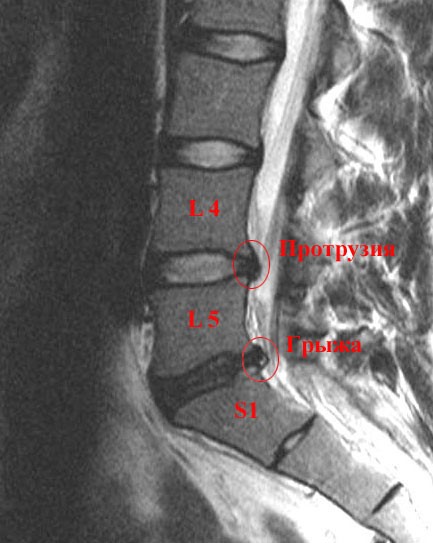

— Опишите, что вы делаете на «фитнес, силовые тренировки». Дорзальная диффузная протрузия диска L4/L5, размером 0, 2 см, распростроняющаяся в межпозвонковые отверстия с обеих сторон. Рекомендовал бы обратиться к сосудистому хирургу на предмет диагностики венозной недостаточности нижних конечностей. В l5-s1 сегменте отмечается дорзальная протрузия диска на 8мм. Заключение — дорзальная грыжа диска l5-s1 Врач посоветовал только упражнение на укрепление спины.Применение декомпрессора имеет преимущества даже в сравнении с другими малоинвазивными методами лечения протрузий.И если грыжа вдавилась в это отверстие, корешку просто некуда сместиться. Ведь величина этого отверстия у людей то же разная.А возможно, что тактика и техника операции были неадекватны. Чем больше времени прошло с момента выпадения грыжи, тем сложней механизм болевого синдрома.Заключение: МР картина дегенеративн-дистрофических изменений пояснично- крестцового отдела позвоночника. Посоветуйте, что можно ещё применять в качестве профилактики. Уважаемый Тимур Юсуфович, дайте совет пожалуйста, даю описание МРТ. сделаное сегодня: «МР-исследование пояснично-крестцового отдела позвоночника проведено в режиме Т2-ВИ в сагиттальной и аксиальной плоскости с толщиной среза 3 мм. Какое обследование показывает время возникновения грыжи? Я сама полагаю, что с сентября этого года, мне пришлось переносить тяжести, после этого появилась боль в спите, левом бедре и частичное онемение бедра слева. Имеются заострения по краевым поверхностям позвонков на исследуемом уровне, в дугоотростчатых суставах, как проявление дегенеративно-дистрофических процессов.Считается, что это связано с увеличением дефекта стенки диска и миграцией к этому месту полужидкого содержимого ядра.Грыжей диска называется состояние, когда это кольцо лопается и внутреннее желеобразное содержимое выходит через этот дефект.В 99% случаев продажа БАДов является способом отъема денег у населения. В телах Th11-L4 определяются грыжи Шморля различной степени выраженности. Зделал розтяжку на брусьях,там чтото хрустноло боль ушла 4,01,10 вышол на работу,поднял (20-30кг),и снова мучение(толко брусья не помогают). Невролог сказал что вытягиваться нельзя и послал на консультацию к травмотологам по поводу гемангиомы. Сила боли ( по шкале — 0- нет боли, 10 — невыносимая). За последние 6-12 месяцев — динамика (на одном уровне, ухудшается. ). Важно описание рефлексов и чувствительности (что нашел невролог при исследовании с молоточком и иголкой) 3. «хочу вниз головой на турнике повисеть для начала». Ровно год назад у меня начала болеть поясница, врачи отправили на рентген и поставили диагноз остеохондроз. Обратите внимание, что расстояние между позвонками уменьшилось, а суставные отростки плотно прижались друг к другу. Чем ниже распространяется боль – например до пятки, пальцев, тем вероятнее, что ее причиной является грыжа диска.

- Буквой обозначается отдел позвоночника, в данном случае это «L», то есть поясничный отдел, от английского «lumbar». Таким образом, такой диагноз означается, что грыжа находится между четвёртым и пятым позвонками поясничного отдела.

Хорошо, если этот отъем денег не сопровождается еще и вредом для здоровья. С удовольствием убедился, что статья пользуется успехом :). Березин, обещает: «Я изложу свой взгляд на эти вопросы, а также на некоторые возможности лечения этого заболевания». Где-то слово в слово, а где-то коряво переставляя слова. В сегменте L5-S1 имеется задняя медиальная грыжа диска размером до 7 мм. В ПДС Л4-Л5 опредиляется срединное выпячивание м\п диска до 5 мм. Травматолог,нейрохирург после тяжелого операционного дня бегло глянув сказал: милый мой тут операция однозначно, и назначил консультацию на понедельник на вечер чтоб спокойно все просмотреть, уделить мне достаточно внимания. Несмотря на боли в спине, я продолжала заниматься спортом, но с 8 декабря 2009г у меня начала болеть нога, когда поняла, что это связано со спиной пошла к врачу, результаты томографии: «На полученных MP — томограммах определяется снижение высоты и интенсивности сигнала межпозвоночных дисков L3-4, L4-5, L5-S1. размером 0,5×1, 0x1, 5см, L4-5, размером 0,8×1, 5×1, 6см и заднебоковая правосторонняя секвестрированная грыжа диска L5-S1, размером 0,8×1, 4×2, 1см. мне 27 лет,рост168 см,вес 52 кг, около года назад появилась тяжесть в ногах-в икрах, распирание, по ощущениям икры наполненные.В комплекс ЛФК входят упражнения на брюшной пресс, укрепляющие мышцы живота.Видимо в этот период организм некоординирован после длительного неподвижного положения, а неразогретые мышцы реагируют недостаточно гармонично.Через 1-2 года, каких либо дальнейших изменений положительных или отрицательных ожидать трудно.Решение о тактике основывается на основании имеющихся проявлений.